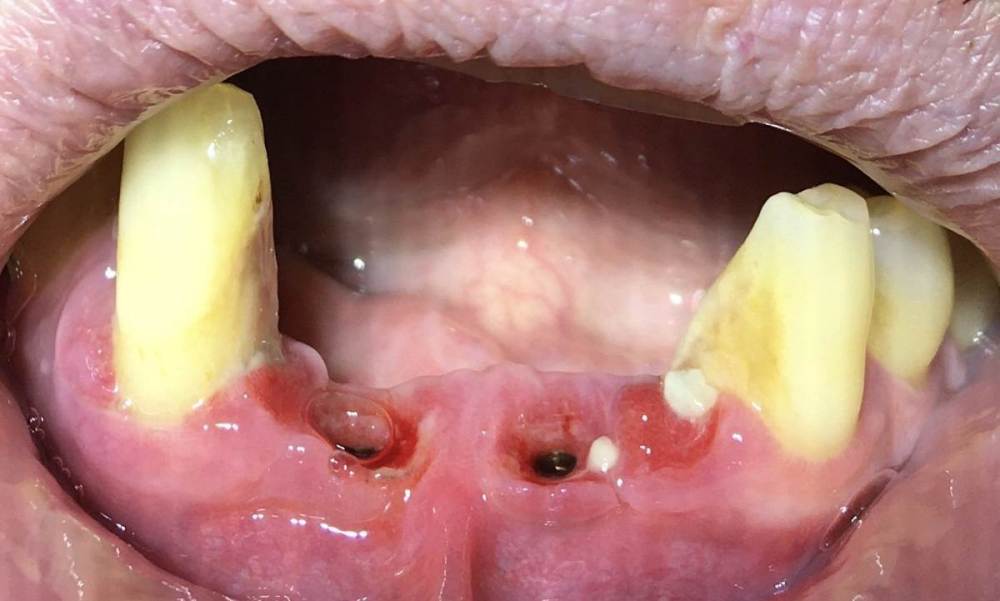

Вот еще фото сразу как сняли коронку 07.07.23 , хорошо что снял.730312457_.thumb.jpg.ca4d73e258835ccdac5df35cc02cd34f.jpg1440661631_1.thumb.jpg.02d3c625a1074bce1c61f0ae06aa1f7d.jpg